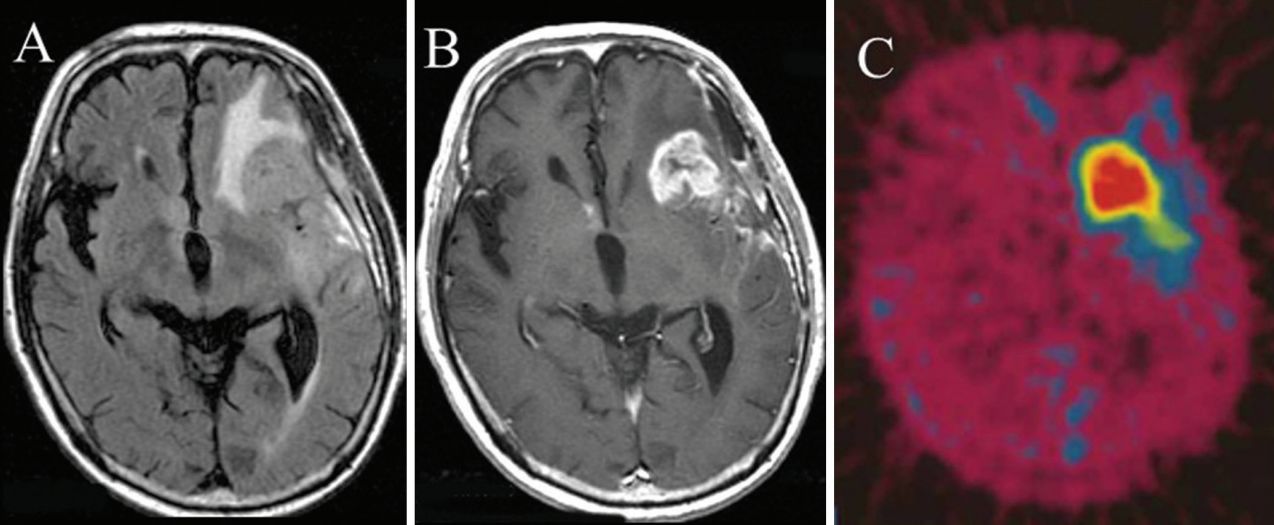

一个典型的胶质母细胞瘤患者的液体衰减反演恢复(FLAIR)和对比增强t1加权磁共振成像(MRI),以及18f标记的硼苯丙胺正电子发射断层扫描(BPA-PET)图像在初始减块手术后。在硼中子捕获疗法(BNCT)之前,患者接受18F-BPA-PET评估肿瘤中的BPA分布和硼浓度,而不直接测定肿瘤中的硼浓度。A: FLAIR, B: gd增强T1加权MRI。C: 18 f-bpa-pet形象。所有的图像都是在初始减容手术后和BNCT前获得的。本例增强肿瘤的脑损伤与正常(L/N)比为7.8。